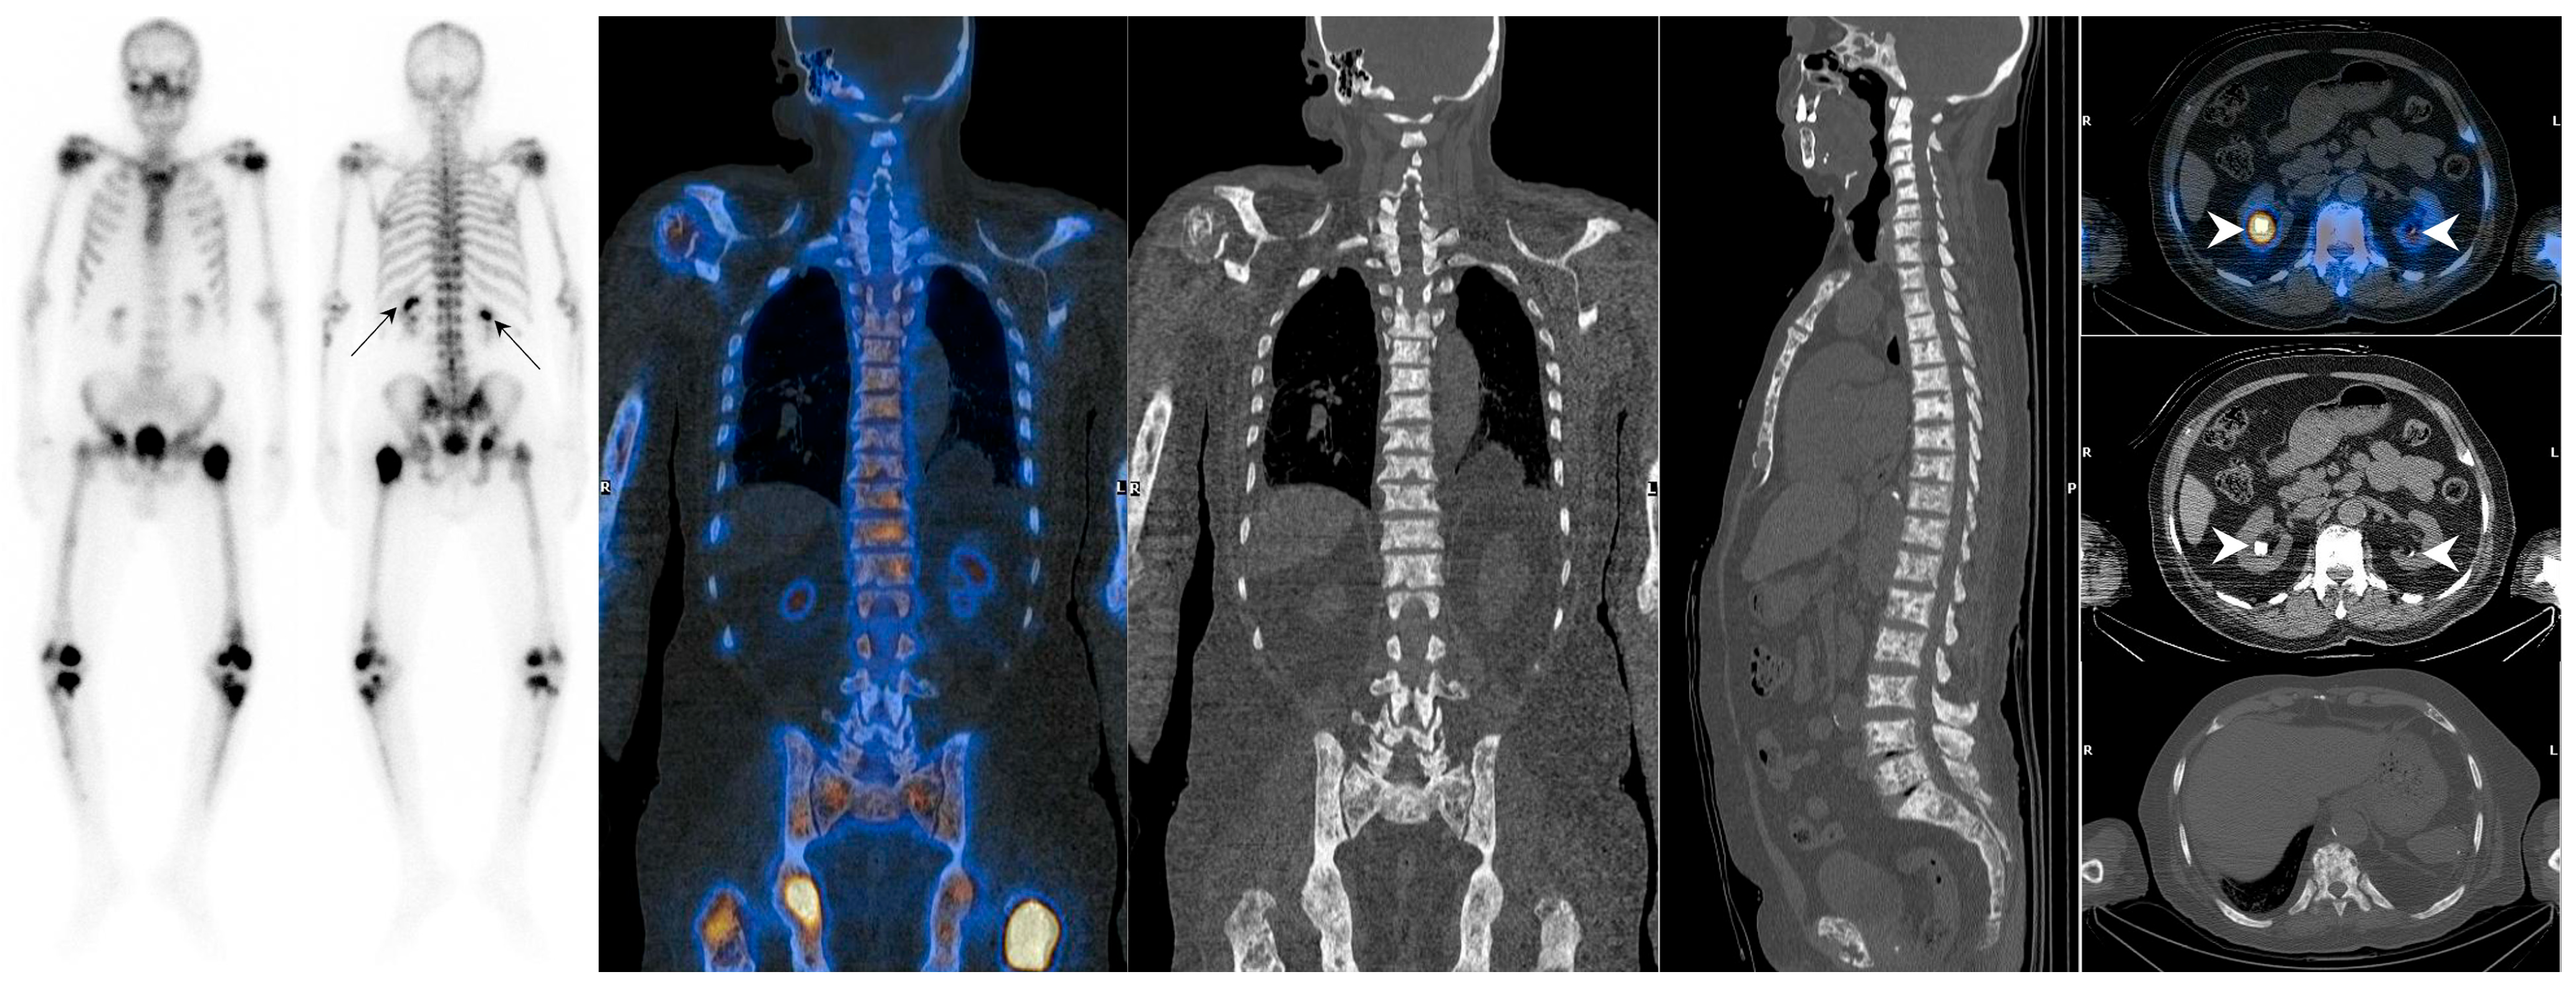

7.1.1. Superscan Pattern in Patients with Prostate Cancer

7.1.2. Dynamic Changes in Prostate Cancer Patients with Superscan